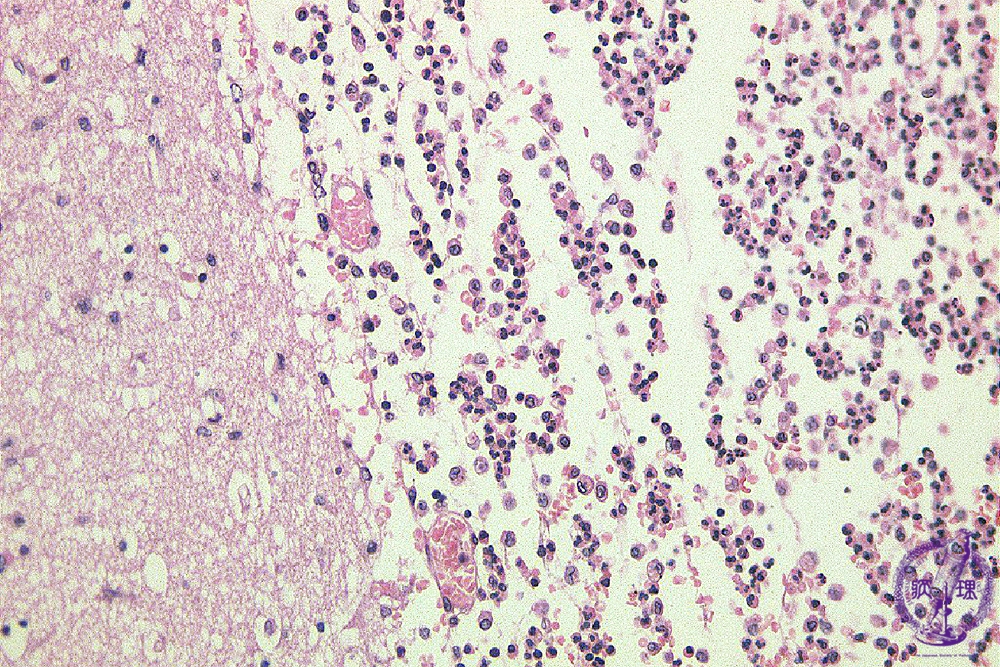

Microscopic findings (H.E. high magnification): Infiltrating inflammatory cells were mainly neutrophils and macrophages.